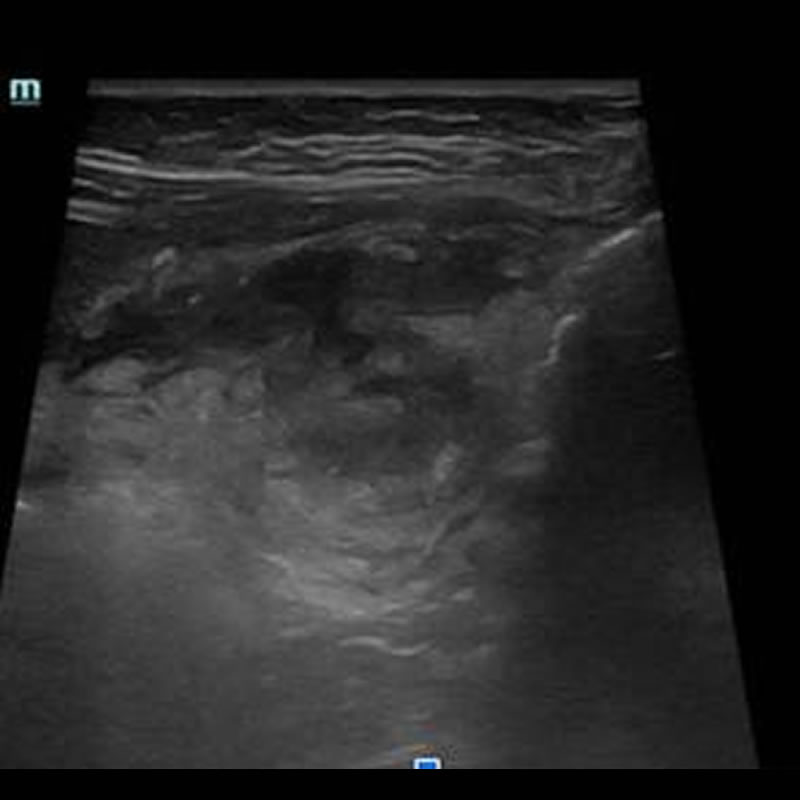

Niño – 4 Años (buen estado general) sin APP. Padres refieren dolor leve de una semana de evolución, localizado a nivel del epigastrio e hipocondrio derecho.